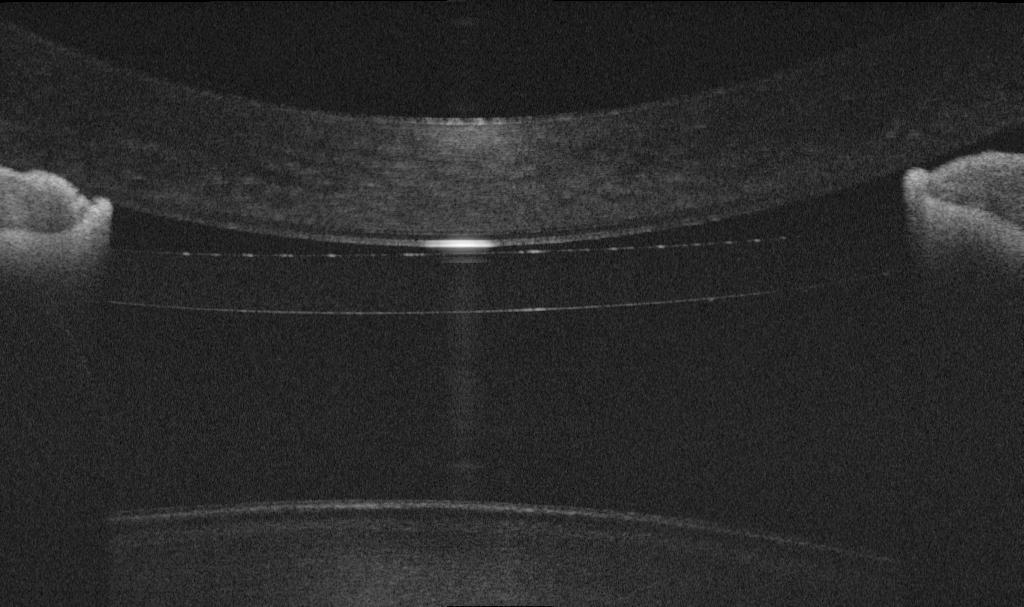

Оптическая когерентная томография переднего отрезка (Optovue SOLIX) визуализирует структуры глаза в формате 3D.

УЗ биомикроскопия (УБМ) позволяет оценить глубину передней/задней камеры, расстояние до хрусталика, форму радужки.